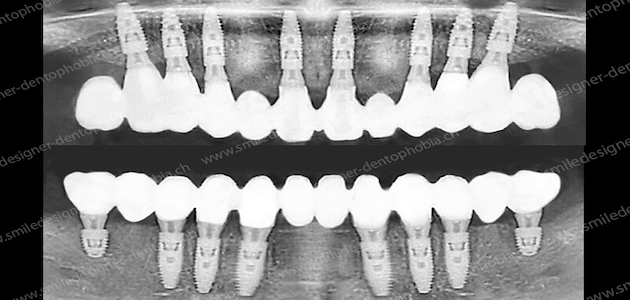

Les affections du parodonte sont des maladies bactériennes qui consument l’os de maintien des racines dentaires. Lorsque ce tissu osseux d’ancrage est détruit, on parle de déchaussement des dents qui peut aboutir à la perte des dents. Les maladies du parodonte sont une des causes majeures de l’édentement de l’adulte.

Les principes globaux des protocoles de soins des parodontopathies sont clairement établis depuis de nombreuses années sur le plan médical ; ils ont peu évolué depuis. Cependant, des progrès dans la recherche ont été réalisés, notamment sur les tissus utilisés et leur application. Des progrès ont été probants dans l’utilisation des matériaux de comblements synthétiques et des membranes collagéniques.